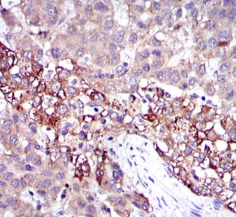

FGG Mouse Monoclonal antibody[4H9C9]

The protein encoded by this gene is the gamma component of fibrinogen, a blood-borne glycoprotein comprised of three pairs of nonidentical polypeptide chains. Following vascular injury, fibrinogen is cleaved by thrombin to form fibrin which is the most abundant component of blood clots. In addition, various cleavage products of fibrinogen and fibrin regulate cell adhesion and spreading, display vasoconstrictor and chemotactic activities, and are mitogens for several cell types. Mutations in this gene lead to several disorders, including dysfibrinogenemia, hypofibrinogenemia and thrombophilia. Alternative splicing results in two transcript variants encoding different isoforms.

Species Reactivity:    Human

Immunogen :   Purified recombinant fragment of human FGG expressed in E. Coli.

IHC    1/200 - 1/1000